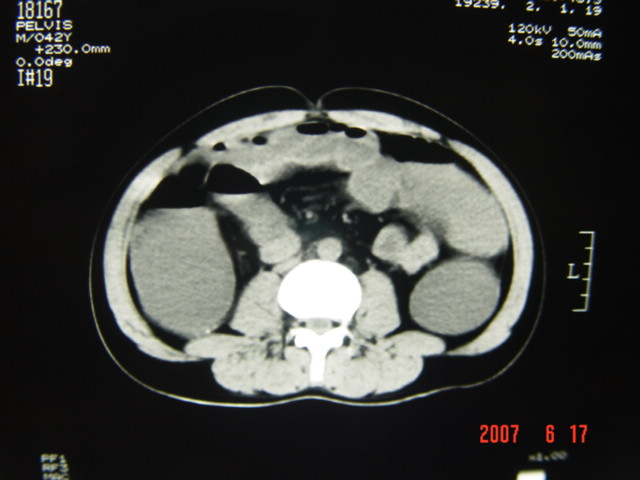

[br][br]以下是引用lkc8963在2007-6-17 13:32:00的发言:[br]完全支持邓主任意见:降/乙交界部占位性病变伴不全梗阻.做个增强或者be可能更好.